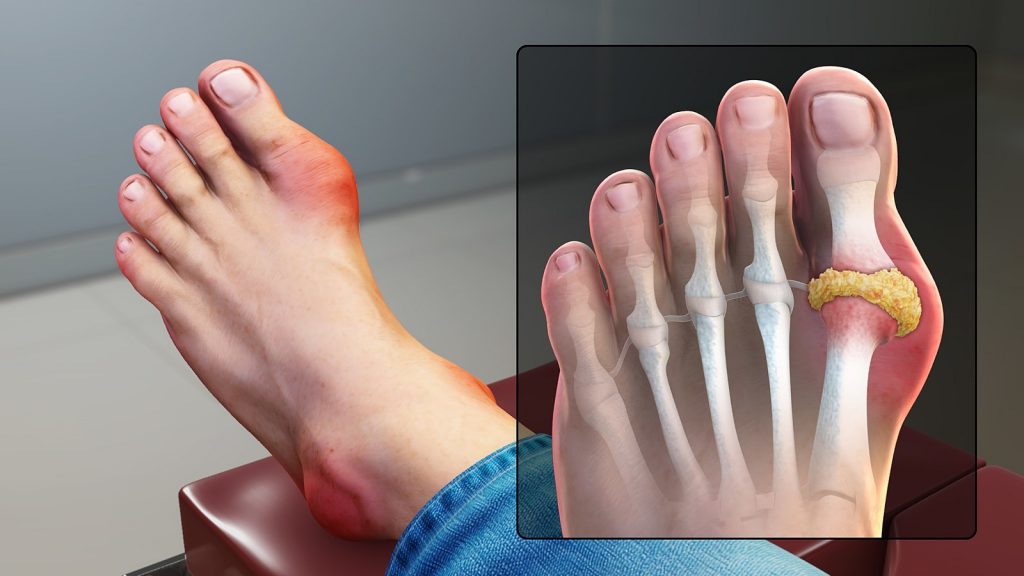

痛风在很大的程度上面,有一点像大脚骨,由于第一跖趾关节痛风石的沉积,表现出来第一跖趾关节凸起很明显,在静止期的时候就有一点像大脚骨,但是痛风和大脚骨呢,又有着本质的区别。

痛风多发生在男性,当然女性也有,男性呢由于体胖者居多。痛风是因为体内的嘌呤代谢异常,出现尿酸的结晶,沉积在全身各处的一种内分泌的疾病,痛风石很容易沉积在第一跖趾关节,当痛风发作的时候,会伴有全身发热的症状,局部发烧全身发烧,局部剧烈疼痛,有些这种疼痛就非常典型非常严重;

但拇外翻呢,也会有在第一只指关节的凸起,以及伴随有脚拇趾偏斜这样的症状,外在症状是这样。我们可以通过拍片看到:痛风石的患者有第一跖趾关节,或者合并其他多部位的痛风石的结晶,痛风的患者还可以出现尿酸的增高,实验室检查出来,尿酸的高也是一个重要的指针;#痛风#